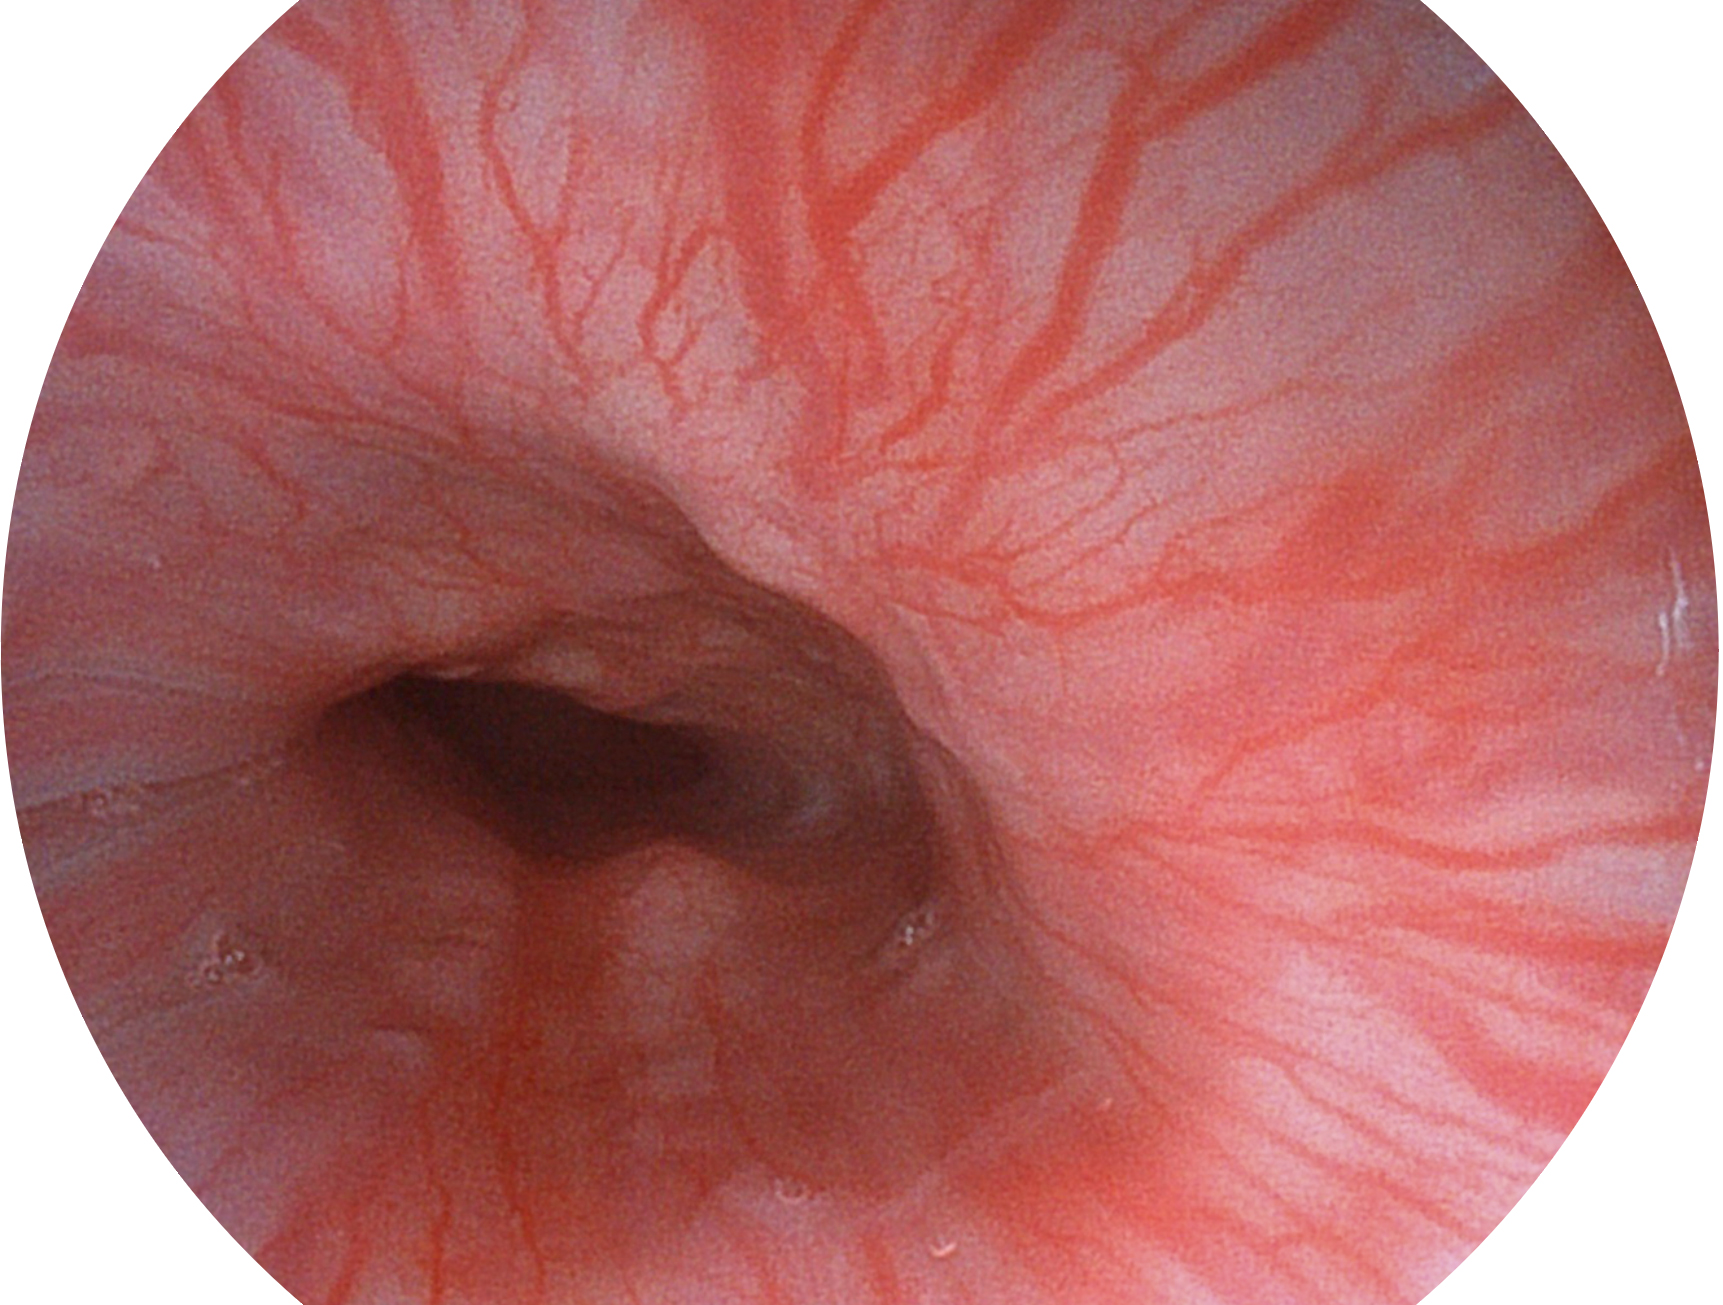

球速体育入口新开发的内镜染色技术,主要是基于多波长LED 光源的开发,VLS-55Q 四波长LED 光源是由四个不同颜色的LED光按照相应照明模式所规定的特定发光比例进行合束后形成,合束后形成的照明光的光谱由红光、绿光、蓝光及蓝紫光这四个不同的波段范围构成。具有更高光谱自由度,通过光谱比例的控制,实现了聚谱成像技术,英文全称为“Spectral Focused Imaging, SFI”,缩写为“SFI”和光电复合染色成像技术,英文全称为“Versatile Intelligent Staining Technology, VIST”,缩写为“VIST”。